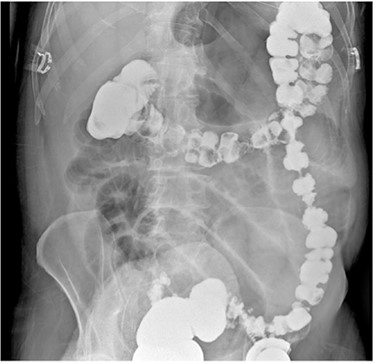

A 67-year-old male with a past medical history of prostate cancer, hypertension and prior open right inguinal hernia repair presented to the emergency department (ED) with sudden onset nausea, vomiting and abdominal pain for 2 h. The abdomen was non-distended and slightly tender in the epigastrium. A clinical diagnosis of pancreatitis was made based on physical examination, history and a mildly elevated lipase and the patient was discharged home with antiemetic medications by the ED providers. The patient presented back to the ED 2 days later with worsening abdominal pain, nausea, vomiting and obstipation. At this time his abdomen was distended and tender to palpation in the epigastrium without peritoneal irritation. Due to his obstructive clinical picture, a CT scan of the abdomen and pelvis with IV contrast (Fig. 1) was obtained in the ED. The scan was read as a possible volvulus versus an internal hernia causing small bowel obstruction. A nasogastric tube was placed after he was admitted to the surgical unit with partial resolution of his abdominal tenderness and distention. A barium enema (Fig. 2) was performed to rule out an obstructing distal mass, which showed a transition point at the hepatic flexure.

Barium enema demonstrating a transition point in the hepatic flexure with contrast angling towards the lesser sac.